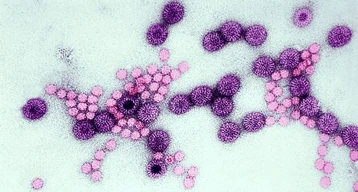

Two men charged with trying to smuggle vials of mpox virus into the US

Killer Virus Outbreak Likely ‘Far Worse’ Than It Seems